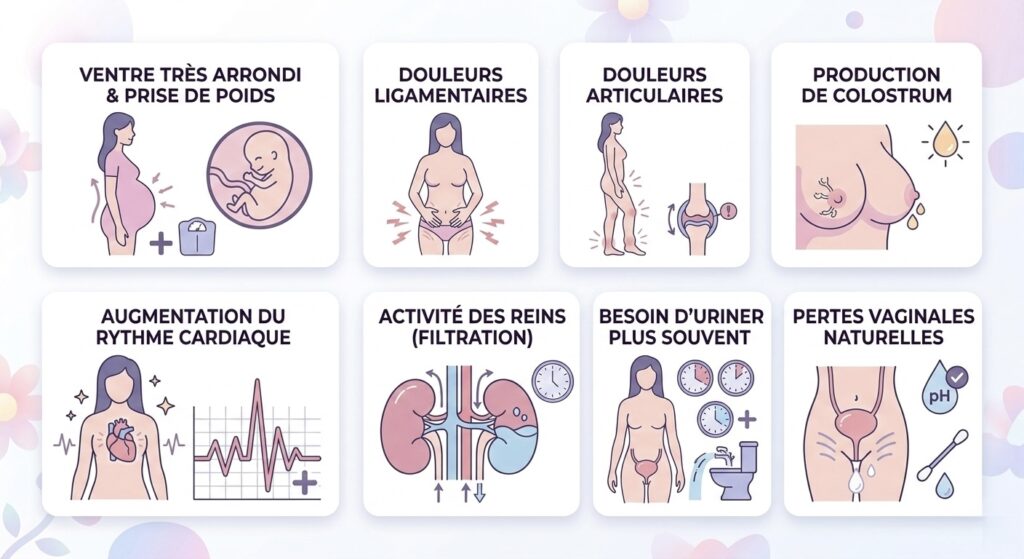

Changement chez la maman

Prise de poids et croissance de l’abdomen et étirement de l’utérus: Le bébé grandit très rapidement et prend du poids, ce qui étire l’utérus. En conséquence, la future mère peut s’attendre à une prise de poids de plus de 5 kilos au dernier trimestre. Elle est essentielle pour achever le développement du bébé et se préparer à l’accouchement.

Changements musculaires et articulaires:Certaines hormones, comme la relaxine, assouplissent les ligaments et les articulations pour l’accouchement, ce qui peut entraîner une sensation de faiblesse dans les articulations, surtout au niveau du bassin, ainsi que des douleurs ligamentaires dans les jambes.

Production de colostrum:Un liquide produit avant l’arrivée du lait maternel peut s’écouler.

Augmentation de la fréquence cardiaque:Le pouls peut augmenter d’environ 10 battements par minute. Le volume sanguin augmente pour combler les besoins du fœtus, ce qui indique une légère anémie.

Augmentation du volume du rein et filtration importante de liquide

Pertes vaginales importantes

- Envie d’uriner la nuit